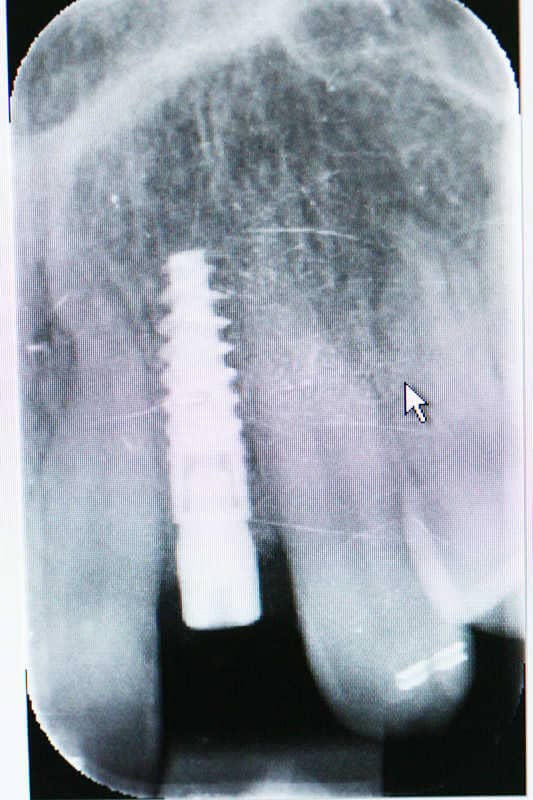

A bal felső perzisztáló - azaz a maradó kismetsző csírahiánya miatt bennmaradt kismetszőt el kellett távolítani, mivel jelentősen mozgathatóvá vált. Rögzített fogszabályozó készülékkel kellő helyet kellett biztosítani az implantátumnak, mely a maradó kismetsző alakú fogat fogja pótolni.

A bal felső perzisztáló azaz a maradó kismetsző csírahiánya miatt bennmaradt kismetszőt el kellett távolítani, mivel jelentősen mozgathatóvá vált.